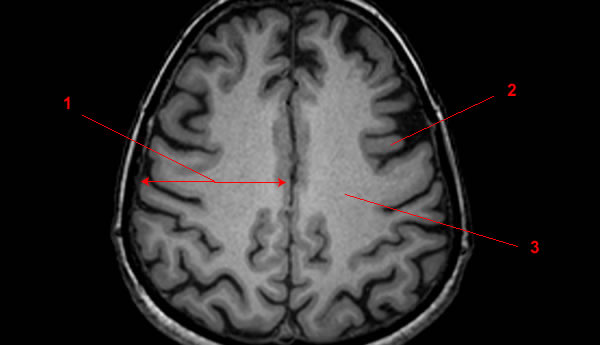

Хроническая ишемия головного мозга и лейкоареоз: симптомы и лечение